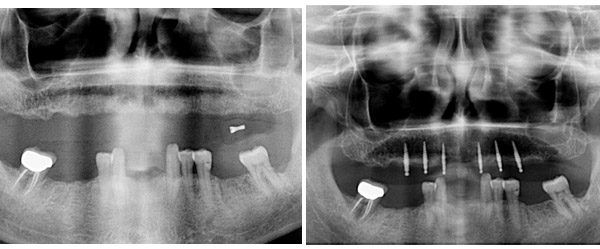

Mini Implant-Supported Denture/Existing Denture Conversion

Mini Implant-Supported Denture